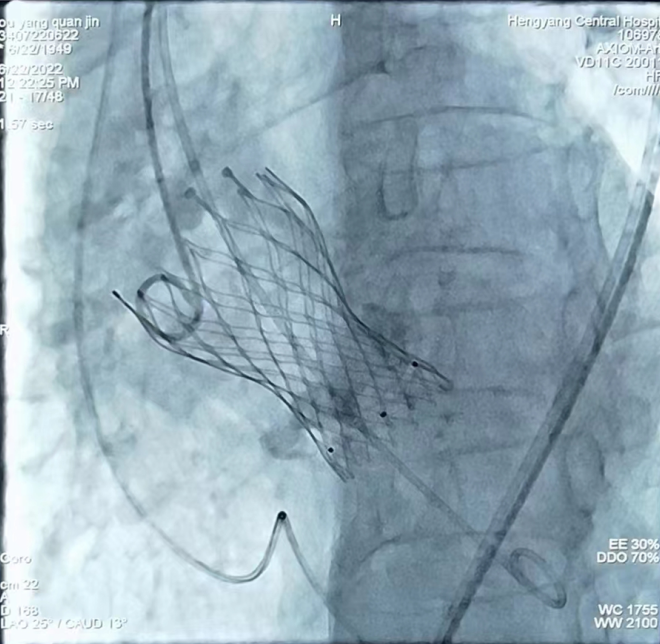

心內(nèi)一區(qū)通訊員何紅丹報(bào)道:為推進(jìn)結(jié)構(gòu)心臟病介入這一先進(jìn)技術(shù)的開(kāi)展,我院組建了以心血管內(nèi)科為主導(dǎo)的TAVR手術(shù)團(tuán)隊(duì),其中包括胸心外科、麻醉科、ICU、手術(shù)室、超聲科專(zhuān)家。6月22日上午,我院在心血管內(nèi)科趙慶禧主任醫(yī)師手術(shù)組及TAVR團(tuán)隊(duì)的通力合作下,又成功開(kāi)展一例TAVR手術(shù),標(biāo)志著我院TAVR團(tuán)隊(duì)在技術(shù)積累、流程優(yōu)化和團(tuán)隊(duì)建設(shè)取得重大突破,是我院TAVR技術(shù)成熟的一個(gè)里程碑。

患者為73歲老年女性患者,心臟彩超示主動(dòng)脈瓣重度狹窄伴輕中度反流,冠狀動(dòng)脈CTA示冠狀動(dòng)脈硬化,主動(dòng)脈瓣多發(fā)鈣化,右冠狀動(dòng)脈近、中段管壁鈣化,管腔稍窄。結(jié)合患者年齡大、心功能差,不能耐受開(kāi)胸?fù)Q瓣等實(shí)際情況,趙慶禧主任組織TAVR團(tuán)隊(duì)對(duì)患者進(jìn)行了縝密的術(shù)前討論,充分評(píng)估了患者主動(dòng)脈瓣及冠脈的情況,并與患者及家屬進(jìn)行了充分溝通,經(jīng)過(guò)反復(fù)研討,制定了一套精密的手術(shù)方案。手術(shù)過(guò)程歷時(shí)3個(gè)小時(shí),患者術(shù)中術(shù)后生命體征平穩(wěn),目前正處于康復(fù)階段。

TAVR手術(shù)即經(jīng)導(dǎo)管主動(dòng)脈瓣置換手術(shù),是一種通過(guò)微創(chuàng)介入導(dǎo)管,將人工心臟瓣膜輸送至主動(dòng)脈瓣區(qū)域并釋放,完成人工瓣膜置入,治療主動(dòng)脈瓣狹窄的手術(shù)。TAVR手術(shù)具有創(chuàng)傷小、術(shù)后恢復(fù)快等優(yōu)點(diǎn),使得部分以前無(wú)法行開(kāi)胸瓣膜置換的患者成功進(jìn)行瓣膜置換成為可能。隨著我院TAVR手術(shù)團(tuán)隊(duì)臨床經(jīng)驗(yàn)的豐富和器械的不斷發(fā)展,TAVR手術(shù)在我院越來(lái)越成熟,標(biāo)志著我院的心臟瓣膜置換進(jìn)入微創(chuàng)時(shí)代,為更多的老年、高危、復(fù)雜性心臟瓣膜病患者帶來(lái)“心”的希望,為衡陽(yáng)乃至湘南地區(qū)老百姓的健康帶來(lái)了福音。